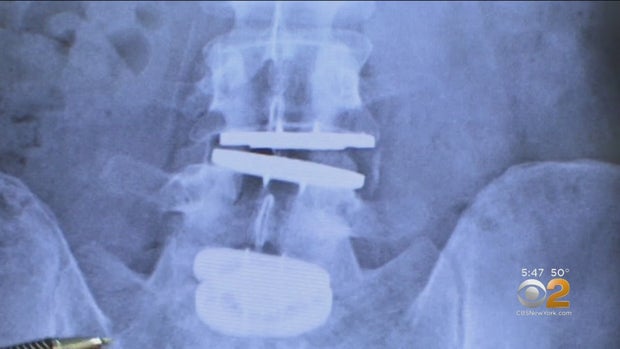

Antonelli's x-rays showed that the artificial discs had failed in two different directions. They needed to come out, but as Dr Vicken Pamoukian explained, that was potentially life-threatening.

Then the next day, Dr. Arutyunyan fused John's lumbar spine with screws and rods.